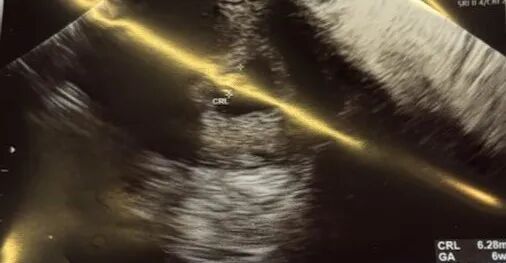

爱妈G一转眼宝宝已经6周了,虽然六周时的胎儿尚未有明显的人类特征,胎儿的体重通常还很轻微,难以具体测量。但它们正在迅速发展,并且这个阶段是整个孕期中发育最为迅猛的时期之一.在孕早期爱妈们都要经历一系列孕妈妈典型的症状,例如晨吐,疲劳,乳房胀痛等等,面对身体的各种变化和不适,希望可以给爱妈们更多的鼓励。期待准爸爸的二宝继续健康成长。

六周零三天的胎宝宝